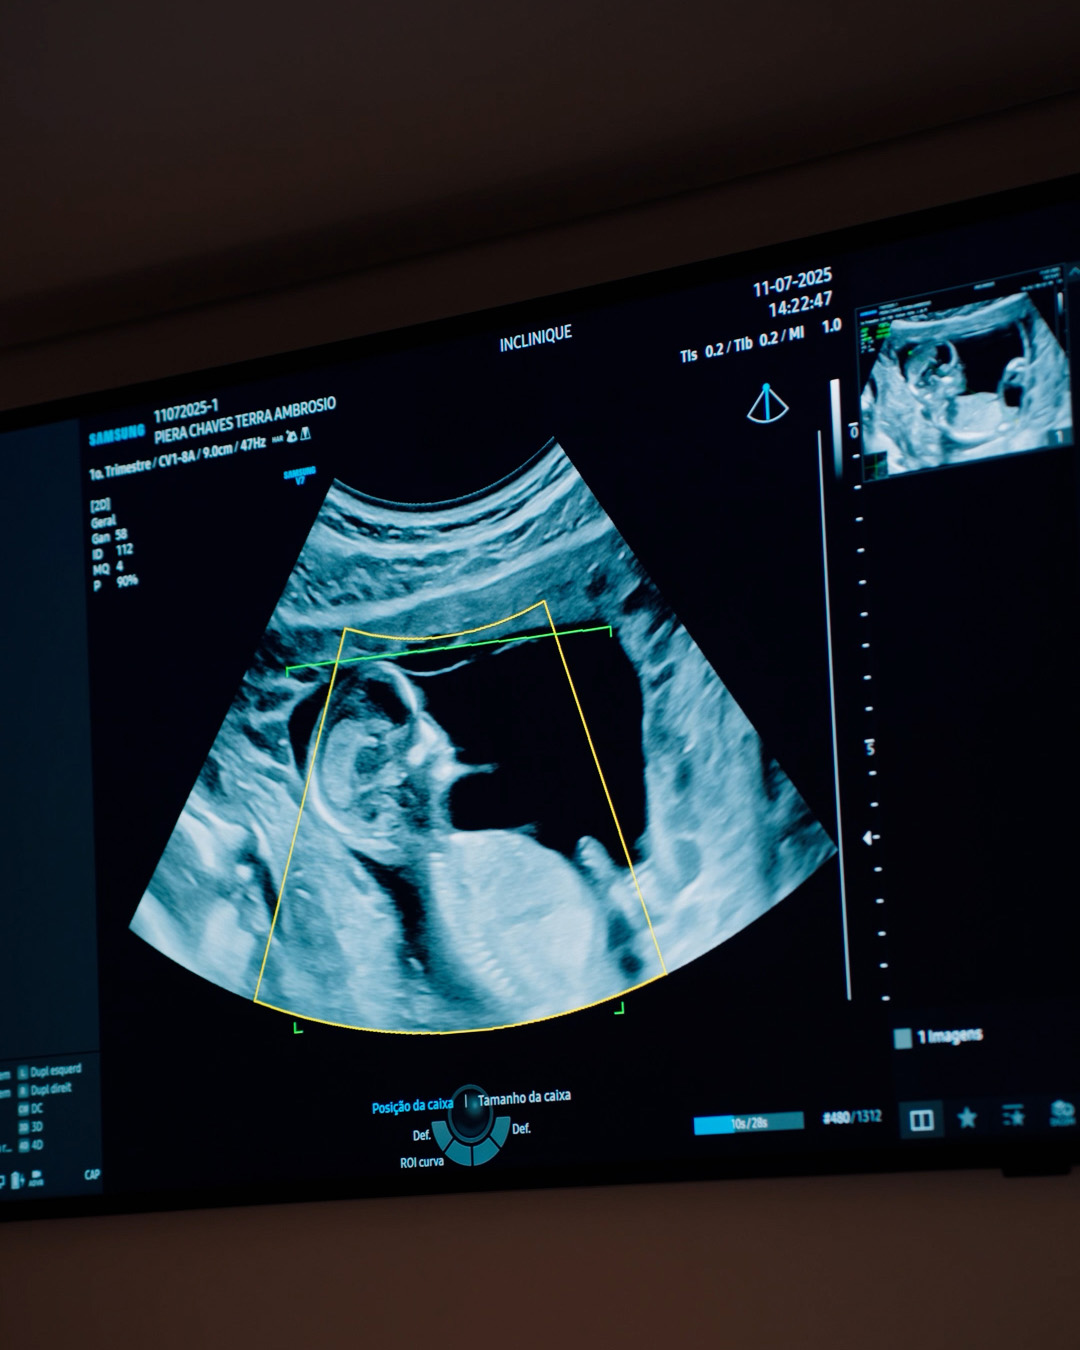

Ultrassonografia obstétrica

Exame de imagem utilizado no acompanhamento da gestação, permitindo avaliar o desenvolvimento fetal, a vitalidade e a idade gestacional, conforme indicação médica.